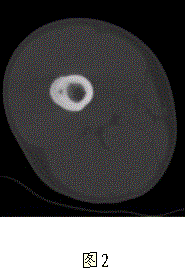

问题 患者男,17岁,右大腿外侧间歇性疼痛逐渐加重近3个月,夜间为重,X线片及CT示右股骨干下段外侧骨皮质梭形增厚硬化,增厚的骨皮质中心隐约可见小圆形低密度灶,骨髓腔未闭合,无外伤史(图1、2)。 与此病变相鉴别的疾病主要是